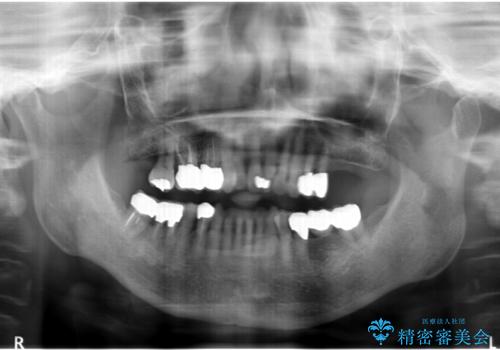

- 歯ぐきからの出血と腫れを主訴に来院された患者様です。

プラークコントロールが非常に悪く、全顎的な歯周病に罹患していました。

「抜歯したくない、インプラントは嫌」という患者様のご希望とご年齢を考慮し、可及的な骨外科処置や根分割術によりできるだけ今ある歯を残す治療方針をたてました。

保存不可能な左上の奥歯2本(左上67)は抜去し、ノンクラスプデンチャーをいれることにしました。

長期的な予後は保証できないことをご了承頂いた上で治療を行いました。